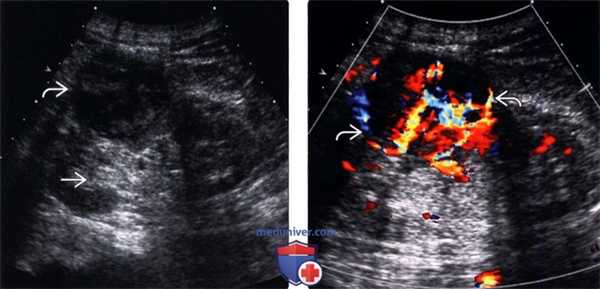

(Левый) На ультразвуковом срезе с цветовой допплерографией визуализируется крупный, гиперэхопенный, гиповаскулярный метастаз в почке. Контуры почки не изменены. Почечные метастазы обычно меньше и менее гиперэхогенные, а также хуже выявляются при ультразвуковом исследовании.

(Правый) На продольном УЗ срезе визуализируется увеличенная, шаровидная почка с гипоэхогенной инфильтрацией коркового вещества при множественной миеломе. Обратите внимание на относительно интактную почечную пазуху.